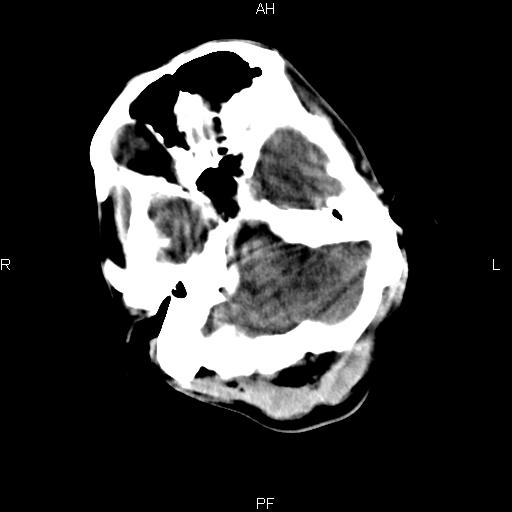

男性,45岁,缄默少语,四肢无力一个月。骨窗未见明确异常。

弥漫性脑白质低密度症

对称性脑白质广泛低密度。有高血压史及大量饮酒史吗?

考虑重度脑白质稀疏症。

弥漫性脱髓鞘病变,建议mri检查。

双侧弥漫性对称性全累及性(外囊亦有累及)脑白质病

患者病程月余,脑沟裂闭合,第三脑室较窄,提示应该有较明显的脑白质水肿,考虑有持续性炎性病变

综合考虑脑白质感染性或非感染性炎症可能性大,不排除为克雅氏病